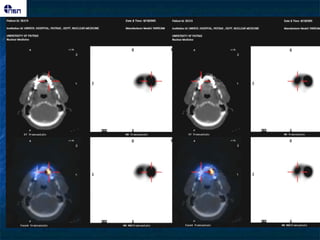

27 αζζεκείξ μεαζαθή εονήμαηα ζε CT, AVS

131I-Norchol Πνόζζηα 3 Ημένεξ Οπίζζηα ???? Πνςημπαζήξ οπεναιδμζηενμκηζμόξ

SPECT/CT IHA Transverse